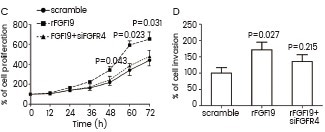

Qiao et al. utilized recombinant FGF19 (Cat#: 12226-HNAE, Sino Biological) to confirm that FGFRs mediate the FRS2α-ERK pathway in HepG2 cells. They found that FGF19 increased the levels of P-FRS2α and P-ERK, shedding light on the signaling mechanisms involved. Hu et al. demonstrated the essential role of FGF19-FGFR4 signaling in ovarian cancer cell proliferation and invasion. They used recombinant FGF19 from Sino Biological to stimulate OVCAR3 cells.

Their results showed that cells cultured with rFGF19 had enhanced cell proliferation and invasion, while FGFR4 knockdown reduced this effect. Lee et al. injected hyperglycemic mice with human recombinant FGF21 from Sino Biological to study the synergistic effect of FOXO1 inhibition and FGF21 in lowering glucose levels in diabetic mice. Their research showed that the combination treatment improved insulin sensitivity.

OVCAR3 cells were cultured with recombinant FGF19 (Sino Biological). Cell proliferation was evaluated using the MTT assay (C), and cell invasion was detected using the Matrigel assay (D). Image Credit: Lingling Hu et al.